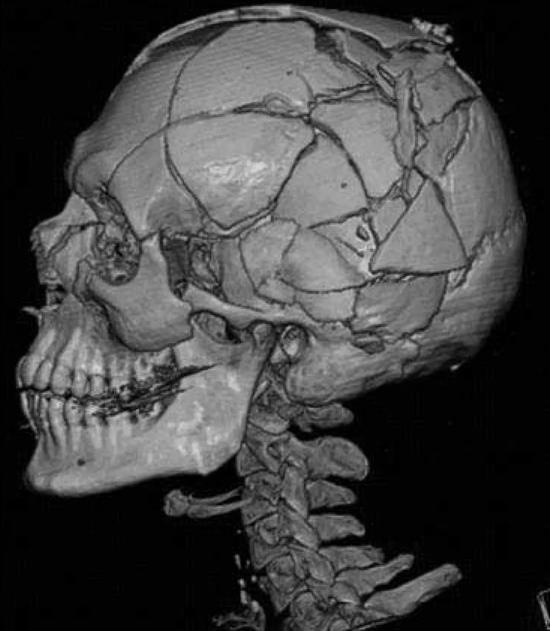

在法医的实际工作中,虚拟尸检的优势还表现在对骨折损伤、心脑血管病变和各类栓塞的检验上。解剖中对骨折部位的探查是一项重要任务,高坠、车祸等案例中复杂的骨折往往会产生较多的骨碎片,切开探查很容易使骨碎片发生位移,往往很难掌握骨折的原始位置关系,对骨折成因的评估难度也会增加。而虚拟尸检无须切开探查就可以确认全部的骨碎片、评估导致骨折的力的方向。甚至可以说,骨折越复杂,虚拟尸检在分析其成因上的优势就越明显。

虚拟尸检对复杂颅骨骨折的清晰呈现